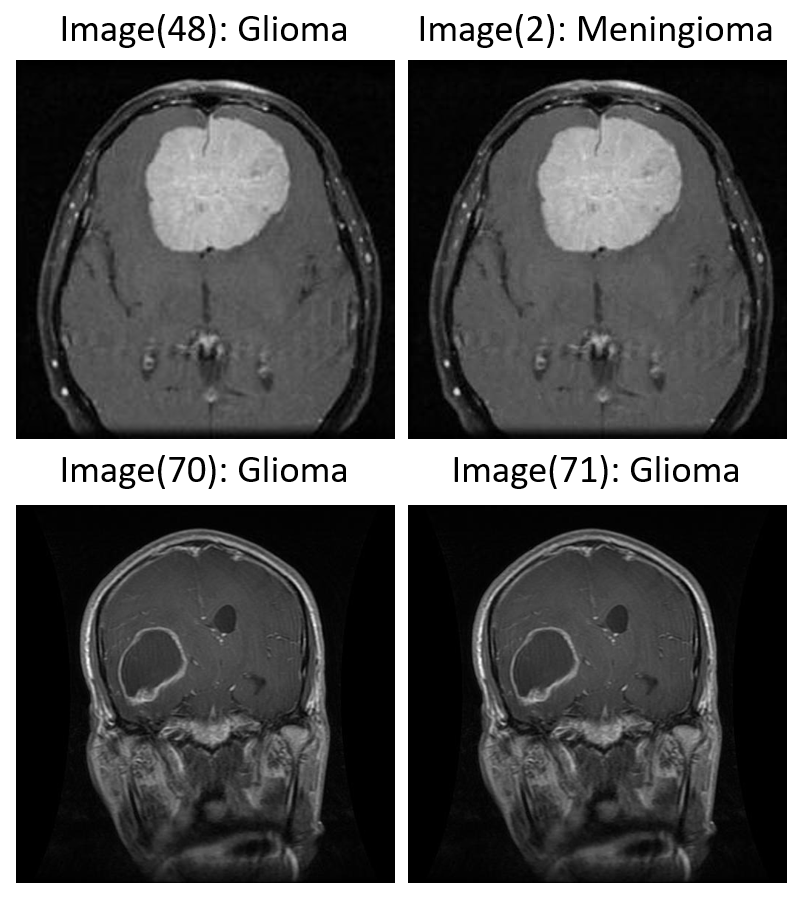

The MRI dataset used in this project contains axial, sagittal, and coronal cross-sectional views of brain scans associated with three major tumor types: glioma, meningioma, and pituitary adenoma. A visual inspection of the dataset reveals significant heterogeneity in scan orientation, contrast, and anatomical presentation—factors that are common in real-world clinical imaging repositories (Figure 1). While the source images were ultimately resized and padded to a uniform 224×224 format for model input compatibility, the original dimensions varied considerably. This non-uniformity highlighted the need for preprocessing to ensure consistent spatial input structure for convolutional neural networks, without compromising the integrity of anatomical detail.

Figure 1: Representative MRI slices across tumor classes showing variation in cross-section and anatomical coverage.

MRI Cross-Sections per Class